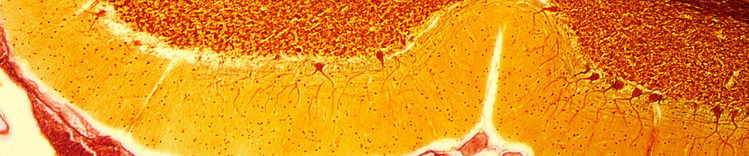

CELLULES DE PURKINJE DANS LE CERVELET